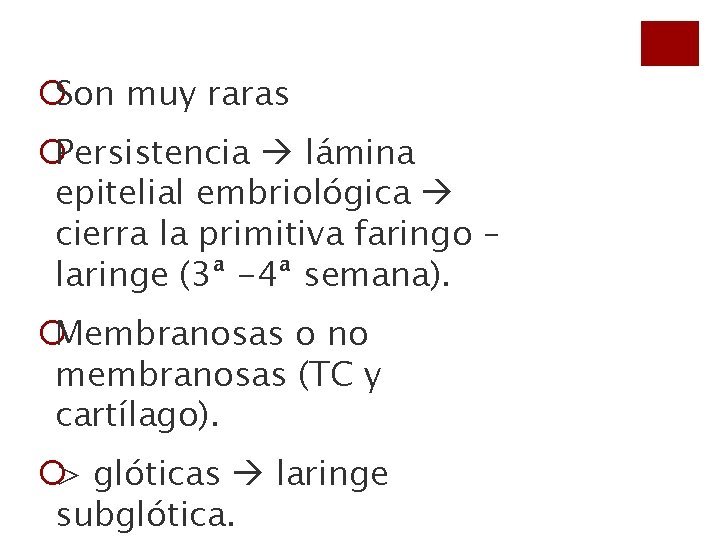

¡Son muy raras ¡Persistencia lámina epitelial embriológica cierra la primitiva faringo – laringe (3ª -4ª semana). ¡Membranosas o no membranosas (TC y cartílago). ¡> glóticas laringe subglótica.